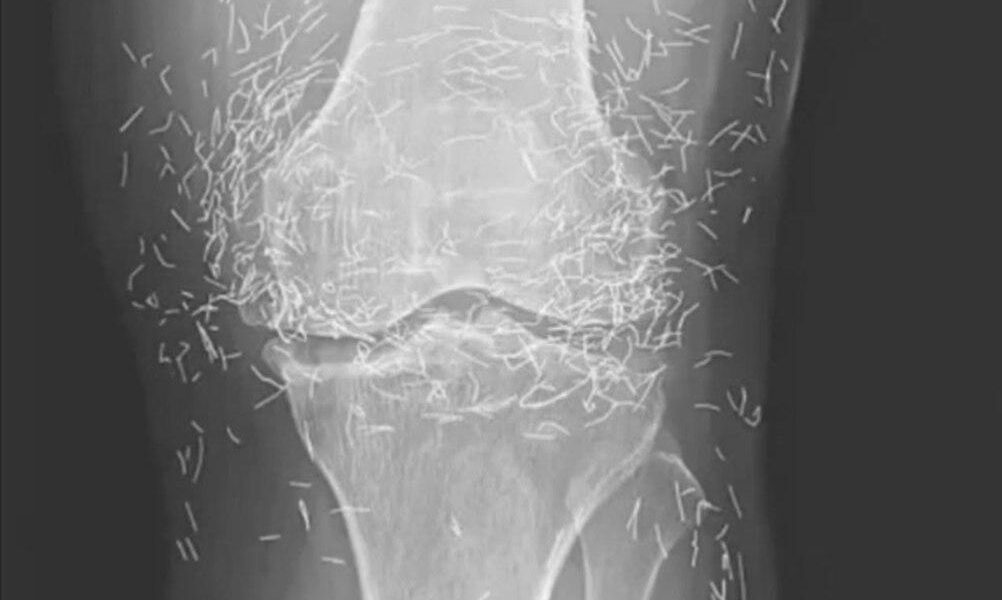

Als eine 65-jährige Südkoreanerin wegen Knieschmerzen in die Klinik kam, rechneten die Ärzte nicht mit einem unerwarteten Fund. Doch genau das machten sie.

Akupunktur, eine jahrhundertealte alternative Behandlungsmethode, besteht darin, Nadeln an bestimmten Punkten des Körpers einzuführen, um Schmerzen zu lindern oder Krankheiten zu behandeln. In diesem Fall wurden die Nadeln – vermutlich aus Gold – absichtlich in ihren Knien belassen, um die Stimulation fortzusetzen.

Er warnte außerdem davor, dass eingebettete Nadeln die Auswertung von Röntgenbildern erschweren können. „Die Nadeln können Teile der Anatomie verdecken“, sagte Guermazi im Jahr 2013.

Noch besorgniserregender ist, dass im Körper verbliebene Nadeln zukünftige medizinische Bildgebungsverfahren gefährlich machen können. „Der Patient kann keine MRT-Untersuchung durchführen lassen, da sich die im Körper verbliebenen Nadeln verschieben und eine Arterie verletzen könnten“, fügte Guermazi hinzu.